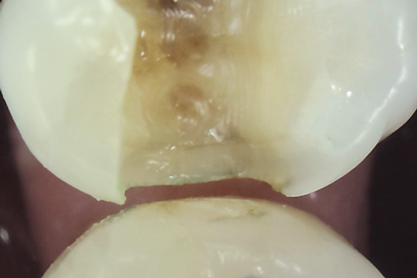

Methylene blue dye is the most commonly used dye to stain cracks because of its pooling tendency.2,3,14,16,17,23 The dye pools into the enamel and dentin cracks, and the tooth is thoroughly rinsed. The resulting dark stain retained in the crack lines then helps enable cracks to be detected (Figure 4 and Figure 5). Methy- lene blue dye, however, also stains dental plaque, requiring the tooth surface to be cleaned with pumice or prophylaxis paste before dye application.14 The dye also can be absorbed by dentin, but any residual dye can be removed using a 10-second phosphoric acid etch.14 A comparative study of dye staining and trans- illumination concluded that methylene blue dye staining and transillumination performed simultaneously is the optimal crack assessment technique.23

Fig 4. Subtle asymptomatic occlusal crack (arrow) of a mandibular right second molar (occlusal view).

Figure 4

Fig 5. Methylene blue dye staining further revealing the occlusal extent of the crack shown in Fig 4.

Figure 5